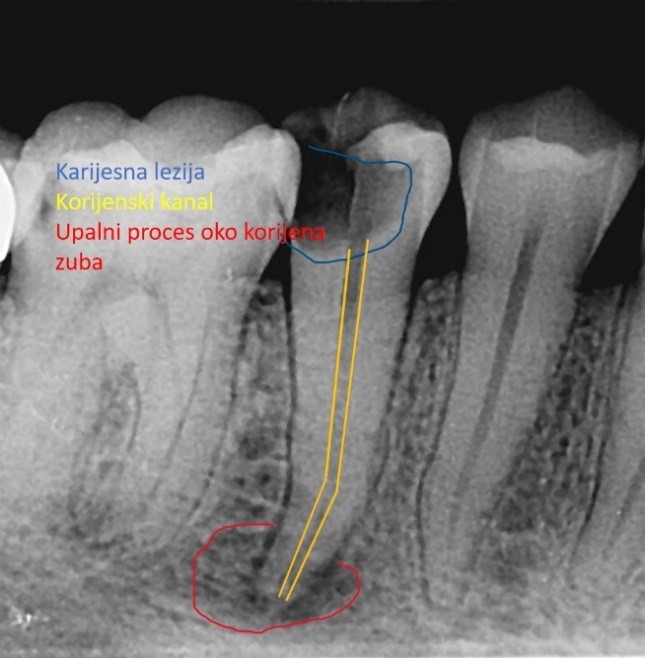

Endodoncija je grana dentalne medicine koja se bavi liječenjem unutrašnjosti zuba (zubne pulpe). Kada bakterije zbog karijesa, dubokog ispuna ili traume prodru tvrde, zaštitne slojeve zuba (caklinu i dentin) zubna pulpa se upali i počinje boljeti, a kada infekcija prodre kroz cijeli korijen, točnije korijenski kanal, doseže područje u kosti koja okružuje zub i tamo razara okolnu kost i uzrokuje upalni proces.

Prikaz velike karijesne lezije i upalnog procesa oko korijena zuba